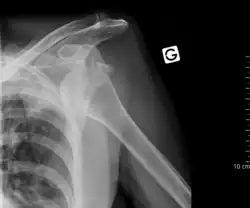

Vykloubení

Vykloubení (luxace) je kloubní zranění, způsobené vychýlením kloubní hlavice z kloubního pouzdra popř. z kloubní jamky.[2]

Vykloubení se obvykle řeší repozicí, tedy lékařským výkonem, při němž se hlavice kosti vrátí zpět na příslušné místo.